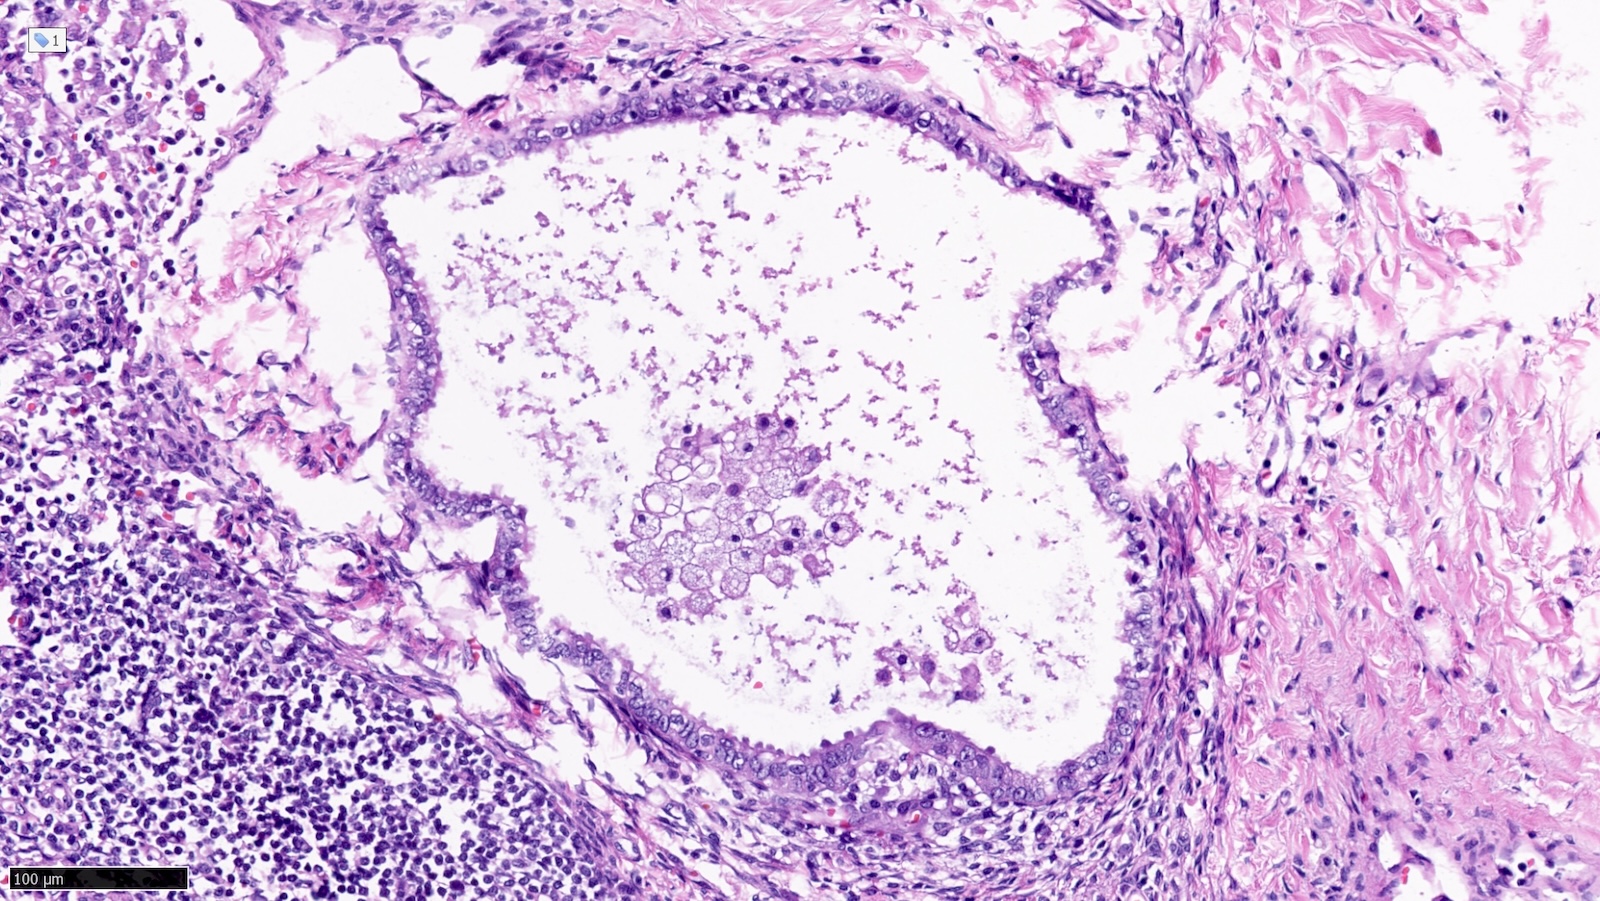

Microscopic (histologic) images

Contributed by Sucheta Srivastava, M.D., Jaya Ruth Asirvatham, M.B.B.S., Rahul Koshy, D.O. and Julie M. Jorns, M.D. (Case #548)

- Endosalpingiosis of axillary lymph nodes (Case Rep Pathol 2016;2016:2856358, Am J Surg Pathol 2010;34:1211, Breast J 2020;26:274):

- Müllerian type glandular inclusions lined by cytologically bland cuboid to columnar epithelial cells that are reminiscent of fallopian tube type lining or coelomic type lining

- Cilia, when present, is a reassuring feature to confirm a benign diagnosis

- Positive for PAX8 and WT1 (good markers of Müllerian origin) and negative for GATA3

Practice question #4

A patient with breast cancer undergoes sentinel lymph node excision. What is the next step based on the histologic findings shown above?

Practice answer #4

B. Confirm epithelial subtype by immunohistochemistry. The histology of the glandular epithelial structure in the lymph node capsule resembles fallopian tube epithelium. PAX8 (positive) and TRPS1 (negative) immunohistochemical stains would further support Müllerian origin and the diagnosis of endosalpingiosis in an axillary sentinel lymph node. Answers A, C and D are incorrect because the patient should not be staged as pN1mi(sn) or receive additional surgery or radiation therapy to the axilla, respectively.